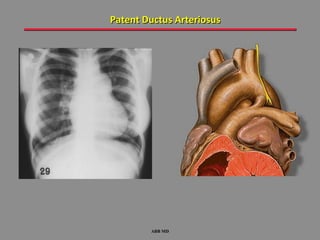

Patent Ductus Arteriosus

ABB MD

Patent ductus arteriosus (PDA) is common in the very preterm infant

with significant lung disease; radiological signs are non-specific